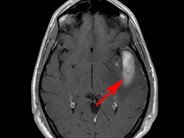

CNS hemorrhage – AML - 1.

MRI from a patient with AML who presented with hyperleukocytosis and developed a temporal lobe hemorrhage (arrow) accompanied by cerebral edema.